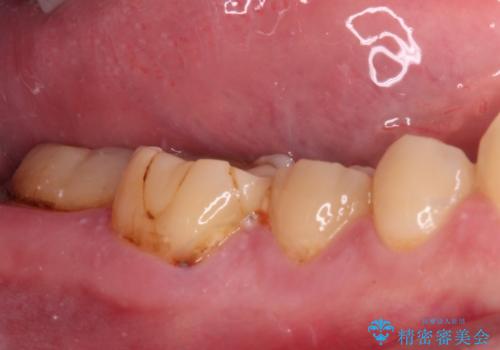

- 左右下顎の奥歯に違和感を感じるとのことで来院された患者様です。

最近ものが挟まりやすくなったり、冷たいものがしみるようになったりと言った症状があり、診査したところ、歯質の欠損や不適修復物などが認められました。

精度の高いセラミックインレーによる修復治療が第一選択となりますが、一方の歯は元々修復物が大きく、咬合力の強い方であったので、セラミッククラウンによる補綴治療を行うこととしました。